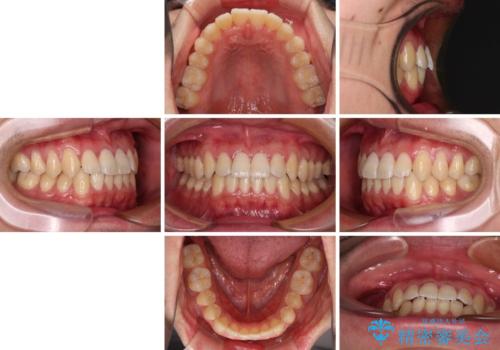

- 上下前歯のデコボコを気にして来院された患者様です。

叢生は軽微であり、費用を抑えて期間もあまりかけずに治療をしたいとのことで、インビザライン・ライトを用いて矯正治療を行うこととしました。

途中通院できなくなり、マウスピースの装着もしっかりとできなかったため、治療期間が長くかかってしまいました。